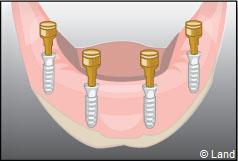

Exemple d’une réhabilitation complète implantaire